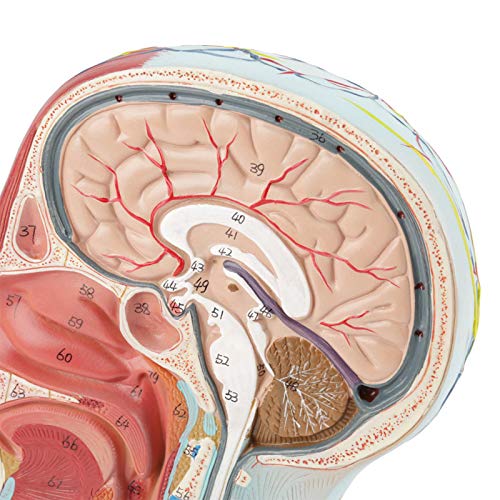

Zeer gedetailleerde getallen gemarkeerd, verdiepen het begrip van de structuur van het menselijk brein, vasculaire structuren

De ene kant toont interne structuur, de andere toont spier- en vasculaire structuur

De ene kant is voorzien van interne anatomie, de andere toont spier- en vasculaire anatomie. Zeer gedetailleerde getallen gemarkeerd, verdiepen het begrip van de structuur van de menselijke hersenen, vasculaire structuren. De gehele structuur is stevig gemonteerd op een kunststof basis, gemakkelijk te observeren. Het model is gemaakt van PVC-kunststof, dat corrosiebestendig, licht is en een hoge sterkte heeft. Toepasbaar op scholen, ziekenhuis, lichamelijke gezondheidsonderwijs, kan als leerhulpmiddel worden gebruikt.

Rode lijn: Artery

Blauwe lijn: Ader

Gele lijn: Zenuw